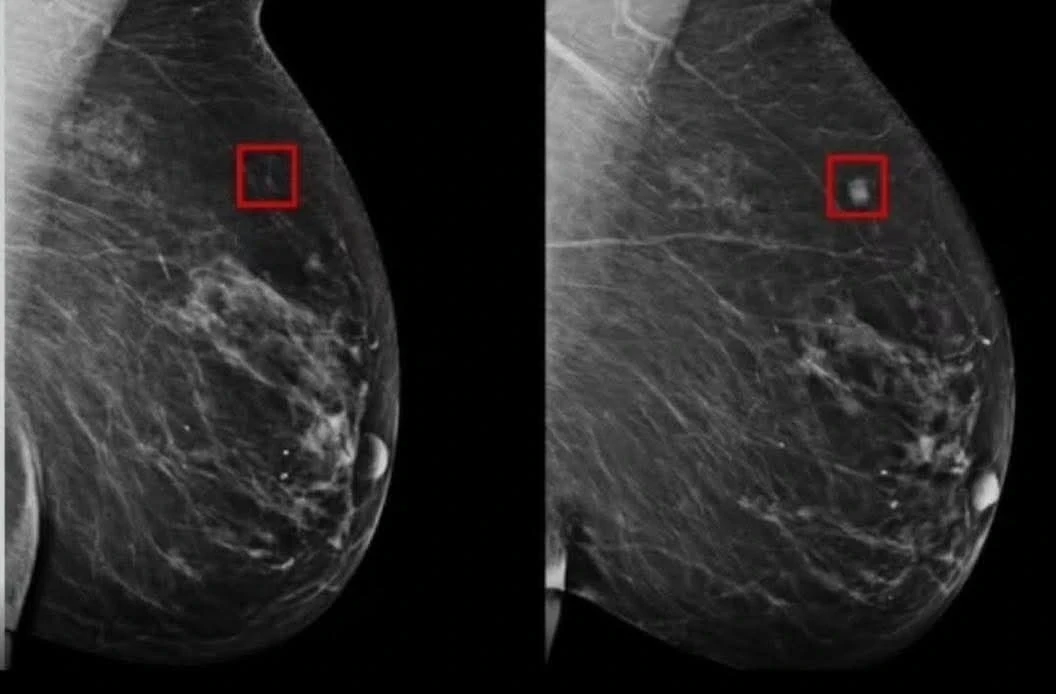

وفي هذا السياق، طوّر باحثون في جامعة ديوك الأميركية نظامًا جديدًا للذكاء الاصطناعي أُطلق عليه اسم AsymMirai، يقدّم مقاربة مختلفة للكشف المبكر عن سرطان الثدي، قائمة على تحليل الفروق الدقيقة بين الثدي الأيمن والأيسر في صور الماموجرام.

فعلى الرغم من أن الاختلافات الطفيفة بين الجانبين قد تكون طبيعية، إلا أن الدراسات تشير إلى أن تزايد عدم التماثل يمكن أن يكون مؤشرًا مبكرًا لاحتمال تطور أورام سرطانية. هذا المؤشر ظل لفترة طويلة غير مستثمر بالشكل الكافي في أنظمة الفحص التقليدية.

تم تدريب النظام على أكثر من 210 آلاف صورة ماموجرام، ما أتاح له التعرّف على أنماط دقيقة يصعب على العين البشرية رصدها، خاصة في المراحل المبكرة جدًا من المرض.

ويتميّز AsymMirai بقدرته على تحليل الفروق الهيكلية والأنسجة بدقة عالية، دون الاعتماد على مؤشرات معقدة أو غير قابلة للتفسير.